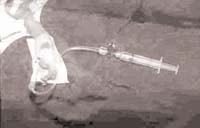

Equipo para canalización arterial

Cánula INSYTE No. 24.

Extensión de anestesia, solución para enjuague, heparinizada con una unidad de heparina por cc. – Bomba de infusión – Férula inmovilizadora – Transductor y monitor para presión arterial (Figura 1).